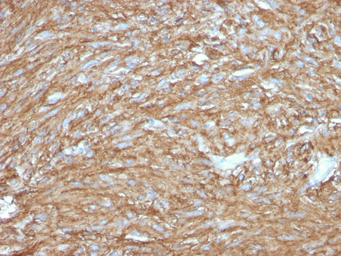

IHC-P analysis of human gastrointestinal stromal tumor (GIST) section using GTX02589 TMEM16A antibody [DG1/2831R].